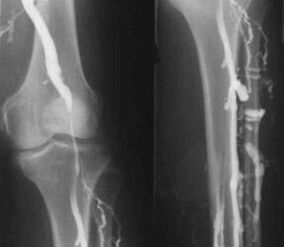

The most common instrumental diagnostic method is the use of ultrasound to examine the venous blood vessels in the legs.This technology allows you to visualize the vascular system and determine the degree of progression of pathological processes.

- Venography.